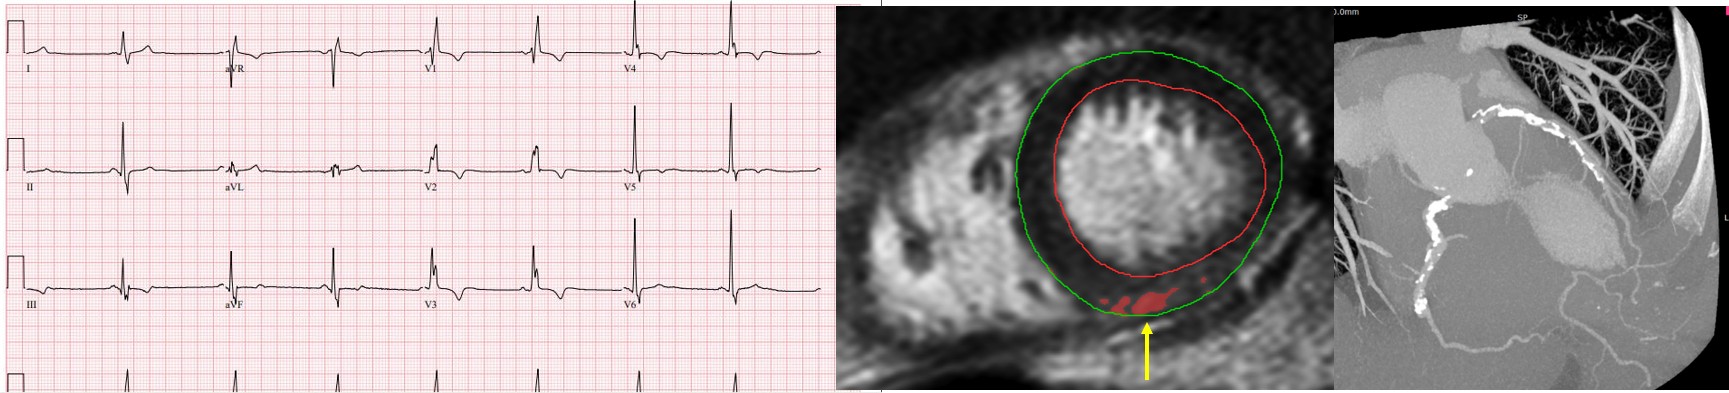

Figure 1. Representative images from a study participant. CMR measured ejection fraction was 62%. The ECG (left) shows sinus bradycardia (heart rate 47 bpm), and right bundle branch block (QRS duration 136 ms) with 4.6% LGE (middle) and extensive atherosclerotic disease (right).